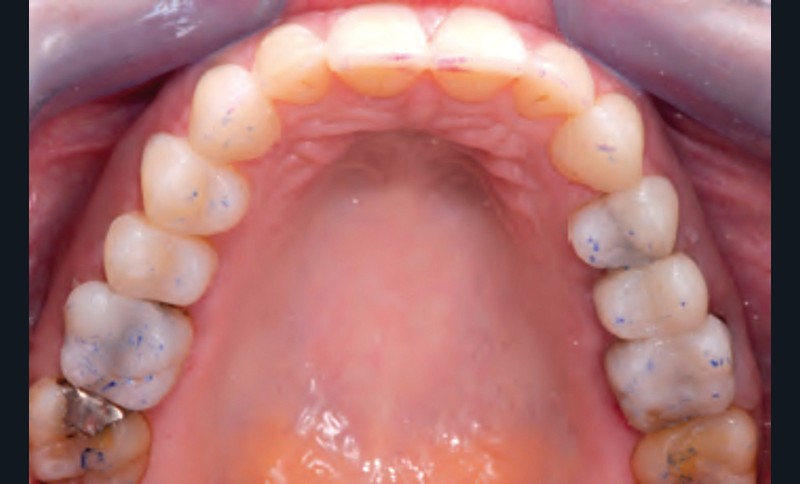

Jean-Pierre Attal : Tout à fait. Mais il faudra donner au prothésiste un maximum d’indications pour qu’il puisse réaliser sa cire de diagnostic. Vous découvrirez que la première étape de la réalisation de ces « full mock-up » est la réalisation d’un projet esthétique virtuel [8] à partir de cadrages photographiques précis aux trois échelles (visage, sourire, dento-gingivale). Gil Tirlet nous expliquera tout cela en détail avec des vidéos que j’ai déjà visionnées et qui sont très impressionnantes (fig. 1 à 4) !

Jean-Pierre Attal : Exactement, car il est possible d’appliquer le protocole de la technique « 3 steps » aux patients présentant des pertes de substance d’origine attritive (bruxisme) (fig. 5).